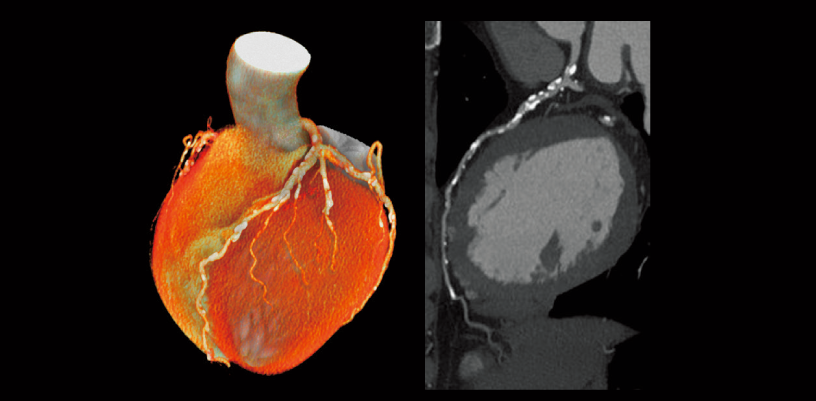

Calificación de la arteria coronaria